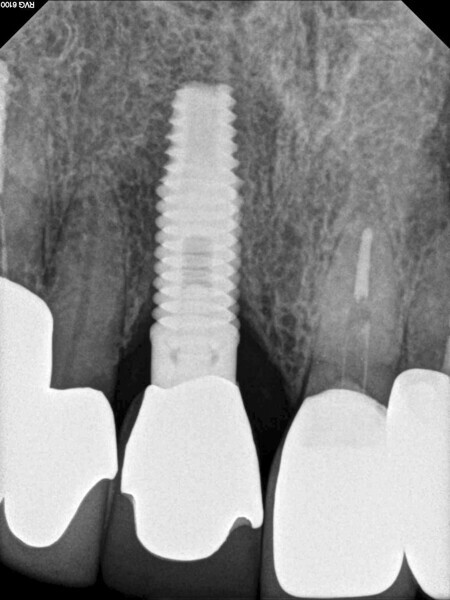

Fig. 13: The pre-op periapical radiograph revealed an existing implant-supported metal–ceramic restoration for the adjacent region #11.

Fig. 18: A periapical radiograph

with a drill in place confirmed that the apex length had been reached and that all the gutta-percha had been removed.